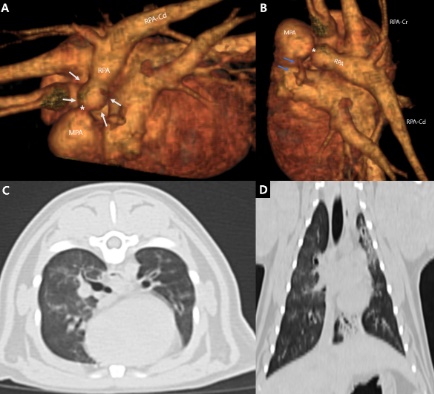

그러면서 면역매개성 사구체신염(ICGN), 변비, 요독증, CKD 관련 미네랄골질환(Mineral Bone Disorder) 등 삶의 질에 영향을 미치는 합병증의 진단과 치료 전략을 소개했다.

유 원장은 “여러 다양한 진단 도구를 활용해 최대한 빨리 진단해 관리해야 한다. 갑상샘기능항진증, 고혈압, 관절질환 등 병발질환에 잘 대응하는 것도 중요하다”고 강조했다.